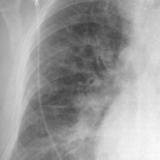

APE 2

Date: 11/05/2005

Views: 2808